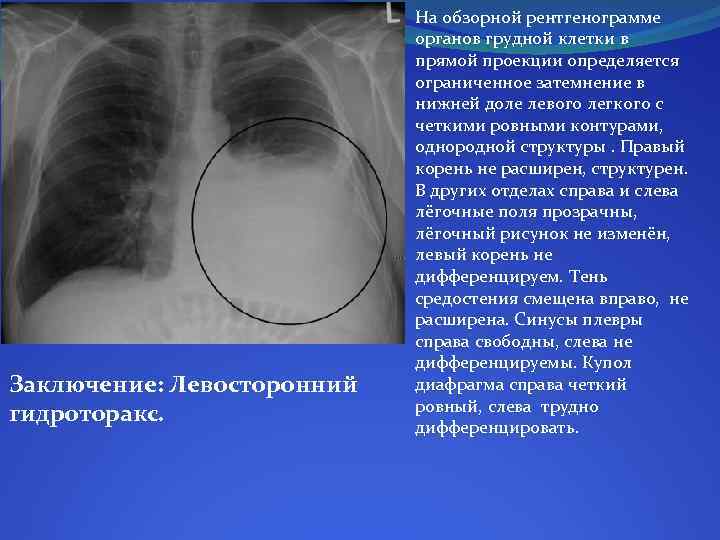

Симптомы и причины скопления воды в легких

Раздел: Ракурсы просвещения